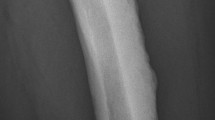

Most radiologists, orthopaedic surgeons and rheumatologists have a special place in their case records for a group of rare musculoskeletal oddities to test their trainees. Melorheostosis must surely be somewhere near the top of any such list when it comes to rare, bizarre and poorly understood conditions with which to challenge all but the most dedicated students of medical curiosities. First described in 1922 as Leri’s disease (On-Line Mendelian Inheritance in Man catalogue-OMIM 155950), there have been fewer than 500 formal reports relating to this sclerosing bone disorder [1]. Even the ancient Greek origins of its name serve to deepen its mystery: melos-limb, rhein-to flow (as in river currents), osteon-bone. By any standards, melorheostosis is a rare condition, estimated to affect fewer than 1 in a million persons. It is not restricted to particular ethnic groups and has no recognised environmental contribution. The classic “dripping candle wax” appearance of the affected bone(s) and its segmental distribution is unmistakable but is a far from constant finding (Fig. 1). Indeed, the precise boundary between melorheostosis and other sclerosing bone conditions (osteopoikilosis, osteopathia striata and various other causes of hyperostosis and osteosclerosis) is somewhat blurred [2,3,4,5,6,7]. Many aspects of the condition are still unexplained or contentious. These include:

Typical features of melorheostosis showing (a) the “melting candle wax” appearance in the affected ulna of a middle-aged woman and (b) unilateral segmental involvement of the left upper limb in a young woman, including the second and third rays of the hand, the ulna and patchy involvement of the carpus (corresponding approximately to the 7th cervical “sclerotome” but bleeding into the 8th sclerotome)

The typical features of melorheostosis, characterised by sclerotic cortical bone in a segmental distribution, should present few diagnostic difficulties [8,9,10], but a range of radiographic patterns have been reported and perhaps only one-third of cases exhibit the classic “dripping candle wax” appearance of the cortex (Fig. 1). There is dense, irregular and eccentric hyperostosis of both periosteal and endosteal bone surfaces, affecting either single or multiple adjacent bones. Typically, either the medial or lateral side of the bone is involved and there is usually quite clear demarcation between the affected and unaffected bone. For diagnostic purposes, four distinct patterns [9] are described (Table 1).